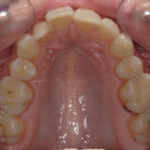

Présentation cas n°1 :